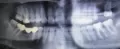

Болят зубы с правой стороны и верх и низ. Все пломбы хорошие. Сделали снимок. Врач говорит, что подстыла, но такие боли были и летом, только не такие продолжительные. Сейчас боль может длиться до часа. Она такая, то заболит сильно, то начинает отпускать. Когда врач посоветовал полоскать горячей водой с солью, я только два раза смогла в рот воды набрать больше не смогла, начали так сильно зубы болеть.